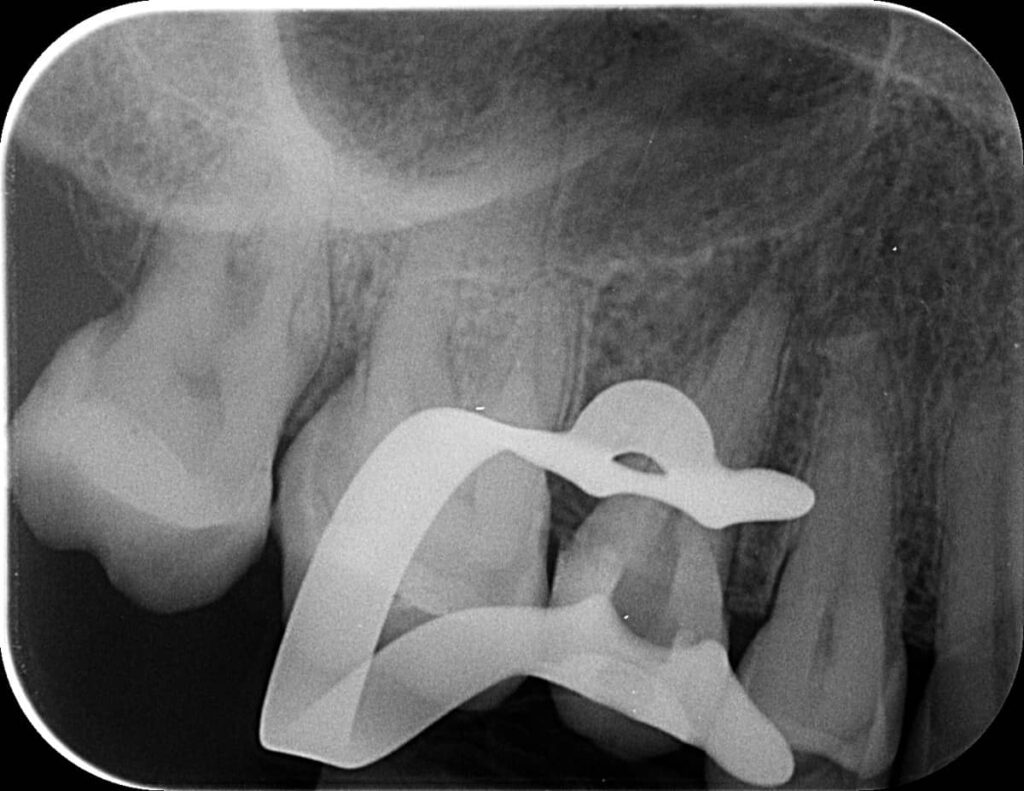

Mivel az eddig kezelt csatornában gond nélkül végig tudtunk haladni, egyértelmű volt, hogy a másik darabka a másik csatornában található. Kis kutakodás után ezt is sikeresen megtaláltuk, és eltávolítottuk. Ezt igazolandó készült egy újabb kontrollröntgen. Az eddig leírt kezelések összesen két alkalmat vettek igénybe, hiszen ez egy időigényes, precíz beavatkozás, hogy a lehető legtöbb saját foganyagot tartsuk meg kezelés közben.

mikroszkópos gyökérkezeléssel megmentett fog: a bent rekedt fragmentumok eltávolítása 3